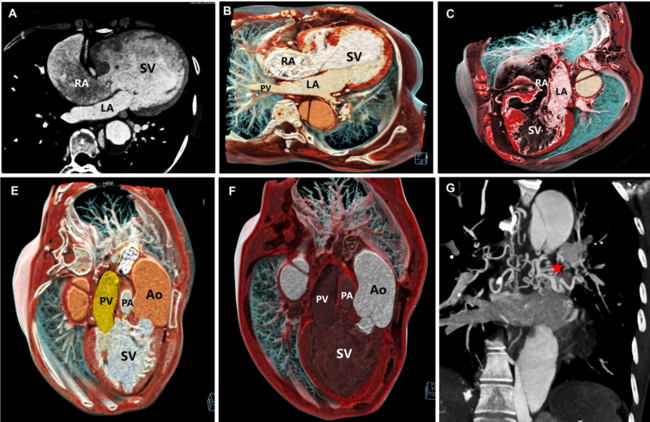

Cinematic Rendering of Single Ventricle Congenital Heart Disease and Body-Pulmonary Collateral Circulation

Video 1. Cinematic rendering from computed tomography angiography of single-ventricle congenital heart disease and body-pulmonary collateral circulation.